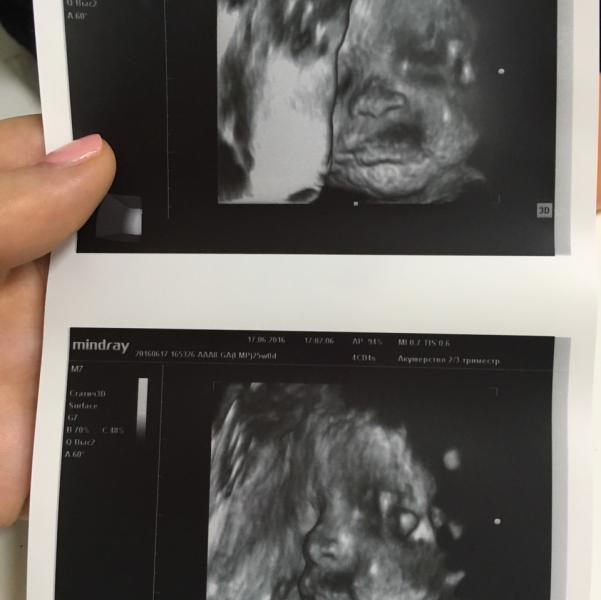

Вот такие у нас щечки ☺️

у нас в 26 недель такие же щечки были. сколько весит?

@tatushka1221, была 790 гр, 2 недели назад 😊 а у вас сколько?

@vik_kadyrmaeva в 24 недели был 921 гр

@katerina060 отчитываюсь по весу. сегодня была на УЗИ, по месячным 31,2 недель, вес 2203 гр